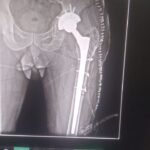

Revision knee replacement surgery is performed when a previously replaced knee joint develops problems such as pain, instability, stiffness, infection, implant loosening, or wear over time.

In this procedure, part or all of the existing knee implant is removed and replaced with new components to restore knee function and reduce pain.

Revision surgery is more complex than primary knee replacement and requires careful planning and expertise. The goal is to improve stability, alignment, and mobility of the knee, helping patients return to comfortable daily activities.